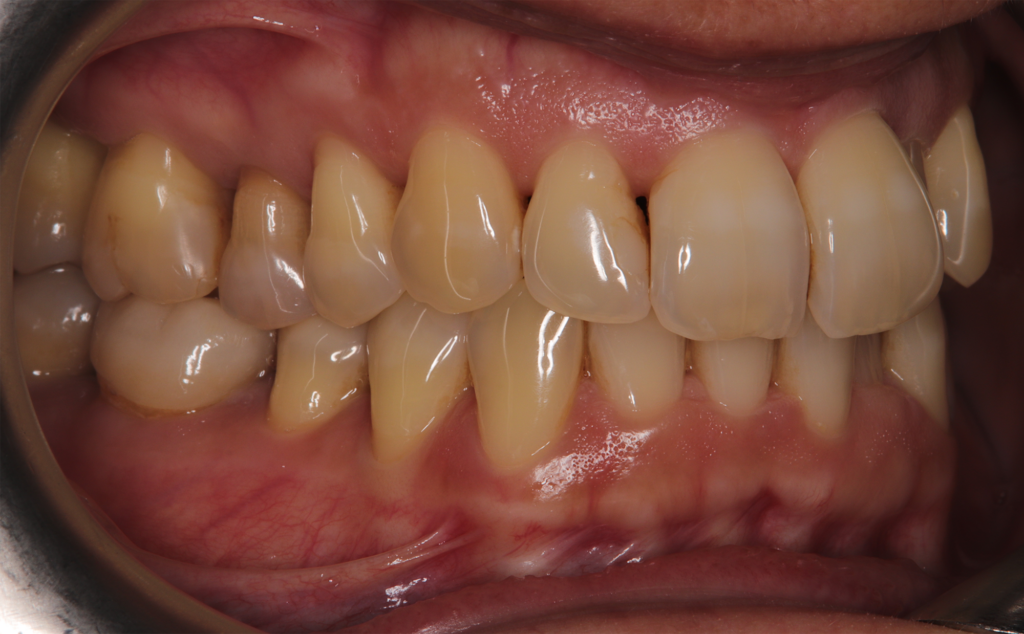

At the conclusion of the treatment, the patient achieved excellent dental alignment and a stable occlusal relationship, particularly in the anterior region. Radiographs and clinical assessments confirmed that there was no further bone loss and that previous improvements were maintained. The aesthetic enhancement from the composite restorations further contributed to the overall success of the treatment.

This case report demonstrates that in patients with a history of periodontal treatment, a carefully modulated orthodontic plan—characterized by reduced tooth movement speed and light forces—can successfully address issues of crowding and anterior crossbite while stabilizing the occlusion and supporting tissues. The favorable outcome achieved with the Spark Advanced system, along with strategic IPR and restorative composite application, supports the adoption of conservative orthodontic protocols focused on occlusal and tissue stability.